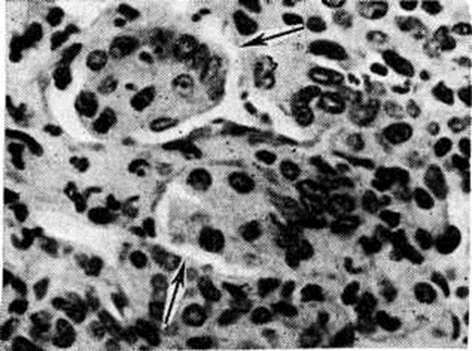

Патологическая анатомияМорфологически изменения при Грипп выражаются повреждениями органов дыхания и токсическим поражением других органов и систем. Выраженность этих изменений зависит от вирулентности возбудителя, состояния специфического и неспецифического иммунитета, а также от характера сопутствующих болезней и бактериальных осложнений. Для местных изменений при Грипп характерны слизистая и вакуольная дистрофия эпителия, частичная гибель его на протяжении дыхательных путей с последующими реактивными изменениями. Характерен серозный, катарально-гнойный, геморрагический и некротический ринит (смотри полный свод знаний), ларингит (смотри полный свод знаний) и трахеобронхит (смотри полный свод знаний Трахеит). В мазках-отпечатках со средней носовой раковины обнаруживается большое количество дистрофизированных клеток цилиндрического эпителия, в цитоплазме которых нередко обнаруживаются оксифильные включения. Наиболее резко поражаются подсвязочная область гортани, трахеи и крупные бронхи (рисунок 1), а также слизистая оболочка языка. Слизистая оболочка — огненно-красная, нередки точечные кровоизлияния и островки желтоватого цвета (очаги некрозов). В более тяжёлых случаях слизистая оболочка трахеи и крупных бронхов на всем протяжении серовато-жёлтого цвета, с небольшими участками кровоизлияний (цветной рисунок 2 и 3). Гистологически эпителий трахеи и бронхов принимает вид аркадообразных структур, возникающих за счёт отёка (смотри полный свод знаний), вакуолизации (смотри полный свод знаний) и отслойки поверхностных слоёв клеток, содержащих вирусный антиген. Часто наблюдается образование фуксинофильных цитоплазматических включений (рисунок 2) и развитие регенераторных (псевдометапластических) процессов. Клетки бронхиального эпителия под действием вируса Грипп теряют ворсинки, количество гранул в них резко уменьшается. Цитоплазматические включения представляют собой аутофагосомы, образующиеся в зоне парциального некроза цитоплазмы вследствие репродукции вируса Грипп (рисунок 3). Резкое полнокровие, отёк и круглоклеточная инфильтрация подэпителиальных слоёв сочетается с утолщением базальной мембраны и усилением секреции образующих слизь желёз. В других местах отмечается гибель эпителия, выраженное полнокровие и лейкоцитарная инфильтрация субэпителиального слоя бронхов и гнойный экссудат с колониями микробов в просвете дыхательных путей. Такого рода очаги гнойно-некротического трахеобронхита служат источником бактериальных поражений лёгочной ткани. При макроскопическом изучении в лёгких отмечается резкое полнокровие, отёк, очаги острой эмфиземы (смотри полный свод знаний Эмфизема лёгких), нередки участки уплотнения интенсивно-красного цвета с гладкой поверхностью разреза, а также гнойный бронхит (смотри полный свод знаний) и бронхиолит (смотри полный свод знаний), участки гнойной, абсцедирующей пневмонии и плевриты (цветной рисунок 3), обычно развивающиеся в случаях присоединения бактериальной, чаще стафилококковой, инфекции («пёстрые» гриппозные лёгкие). Гистологически часто обнаруживают очаги ателектаза, утолщение межальвеолярных перегородок за счёт белкового пропитывания и полнокровия, дистрофию и десквамацию альвеолоцитов. В просвете альвеол, кроме разрушающихся альвеолоцитов, обнаруживаются немногочисленные макрофаги и лейкоциты, взвешенные в серозной жидкости, местами распадающиеся лейкоциты или отёчная жидкость с колониями микробов. Бронхопневмонии (смотри полный свод знаний Пневмония), зачастую вызываемые стафилококками, склонны к абсцедированию с последующим прорывом в плевральную полость. Эпителий бронхов при этом погибает на большом протяжении. Стенки сосудов лёгкого утолщены за счёт плазматического пропитывания, эндотелий нередко гиперплазирован. Наряду с явлениями стаза (смотри полный свод знаний) местами видны тромбы, связанные с очагами стафилококковой инфекции. В случаях злокачественного течения Грипп, зачастую связанного с бактериальными наслоениями, явления полнокровия лёгких и внутренних органов выражены резко, а клеточные реакции оказываются подавленными, что объясняется сочетанной гриппозно-стафилококковой интоксикацией. Характерным для такой молниеносной формы Грипп является развитие токсического геморрагического отёка лёгких (смотри полный свод знаний).